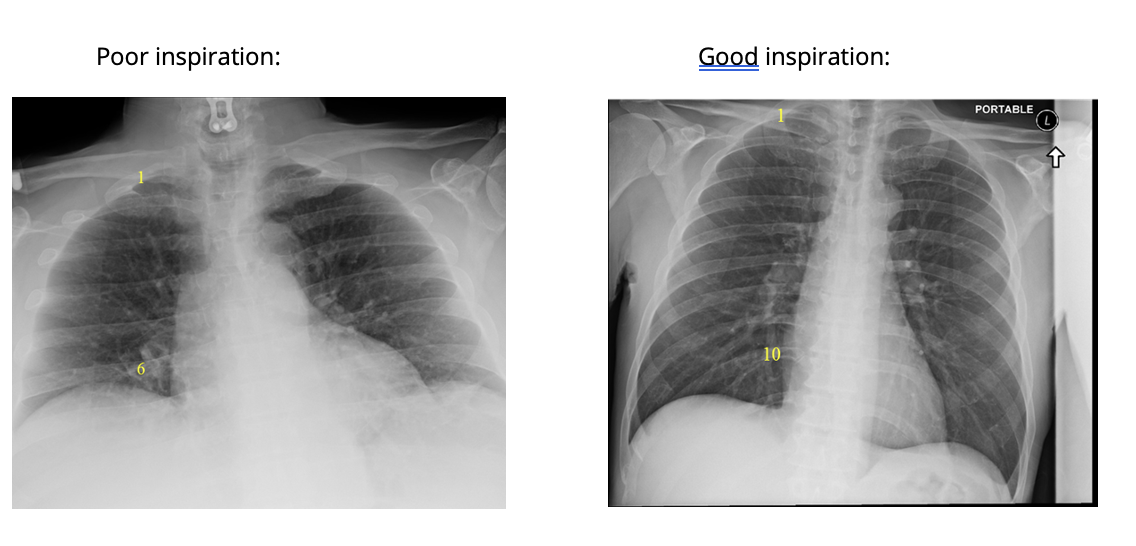

Q

How can you tell if a CXR has been taken during a good inspiration?

Count the anterior ribs on the right → 6 anterior ribs should be visible above the right hemidiaphragm

Anteriorly, which rib should intersect the diaphragm and where?

A

8

How can you assess for hyperexpansion on a CXR?

1. Count ribs → >7th anterior rib intersecting the diaphragm at the mid-clavicular line

2. Check for flattening of hemidiaphragms